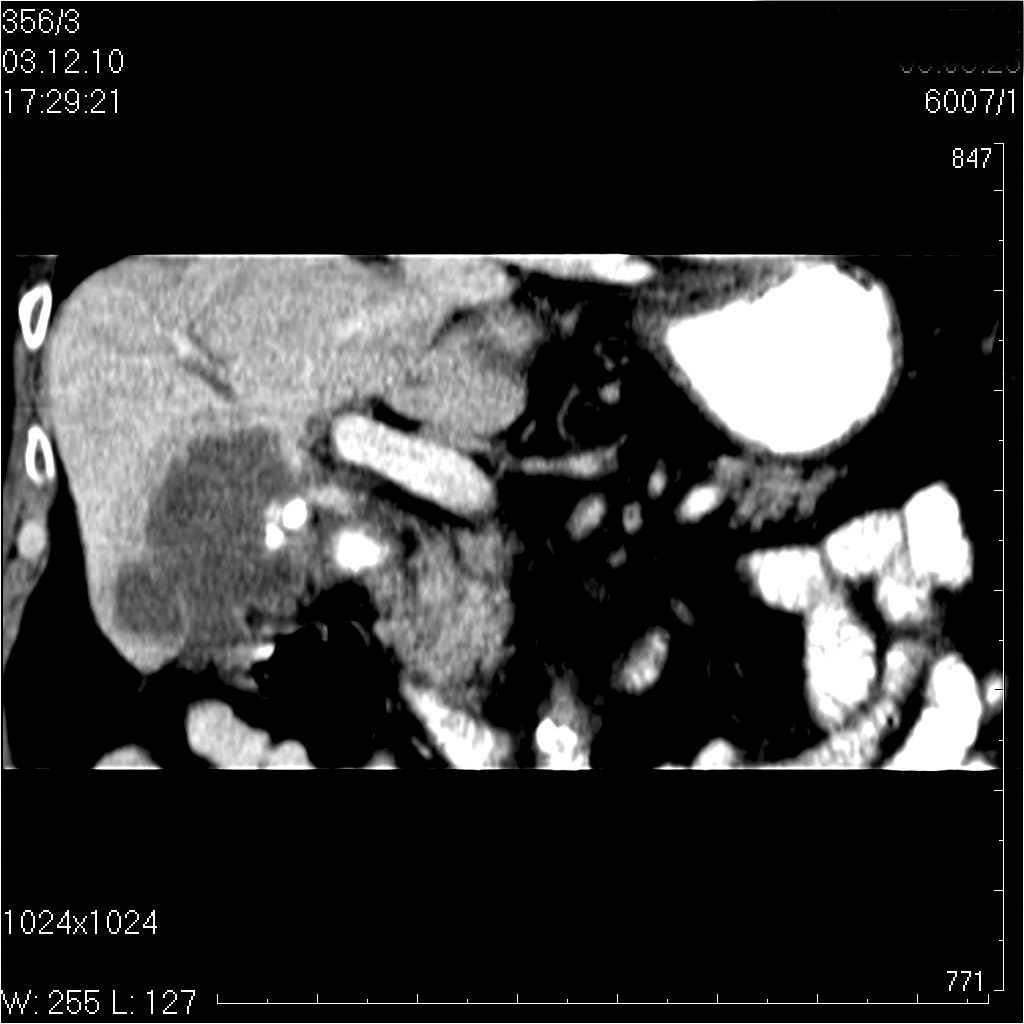

Пожилой мужчина с невыраженными болями в правом подреберье.

видео КТ

Диагностическая лапаротомия - Рак желчноо пузыря с прорастанием в паренхиму печени

tags: gallbladder, adenocarcinoma, cancer, ultrasonography, CT